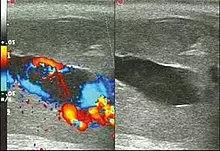

Ultrasonography

Color Doppler ultrasound demonstrating a hypoechoic collection that corresponds to hematoma with arteriovenous fistula secondary to traumatic injury of the penis due to impact with bicycle handlebars, resulting in high-flow priapism.[11]

Penile ultrasonography with doppler is the imaging method of choice, because it is noninvasive, widely available, and highly sensitive. By means of this method, it is possible to diagnose priapism and differentiate between its low- and high-flow forms.[11]

In low-flow (ischemic) priapism the flow in the cavernous arteries is reduced or absent. As the condition progresses, there is an increase in echogenicity of the corpora cavernosa, attributed to tissue edema. Eventually, changes in the echotexture of the corpora cavernosa can be observed due to the fibrotic transformation generated by tissue anoxia.[11]

In high-flow priapism normal or increased, turbulent blood flow in the cavernous arteries is seen. The area surrounding the fistula presents a hypoechoic, irregular lesion in the cavernous tissue.[11]